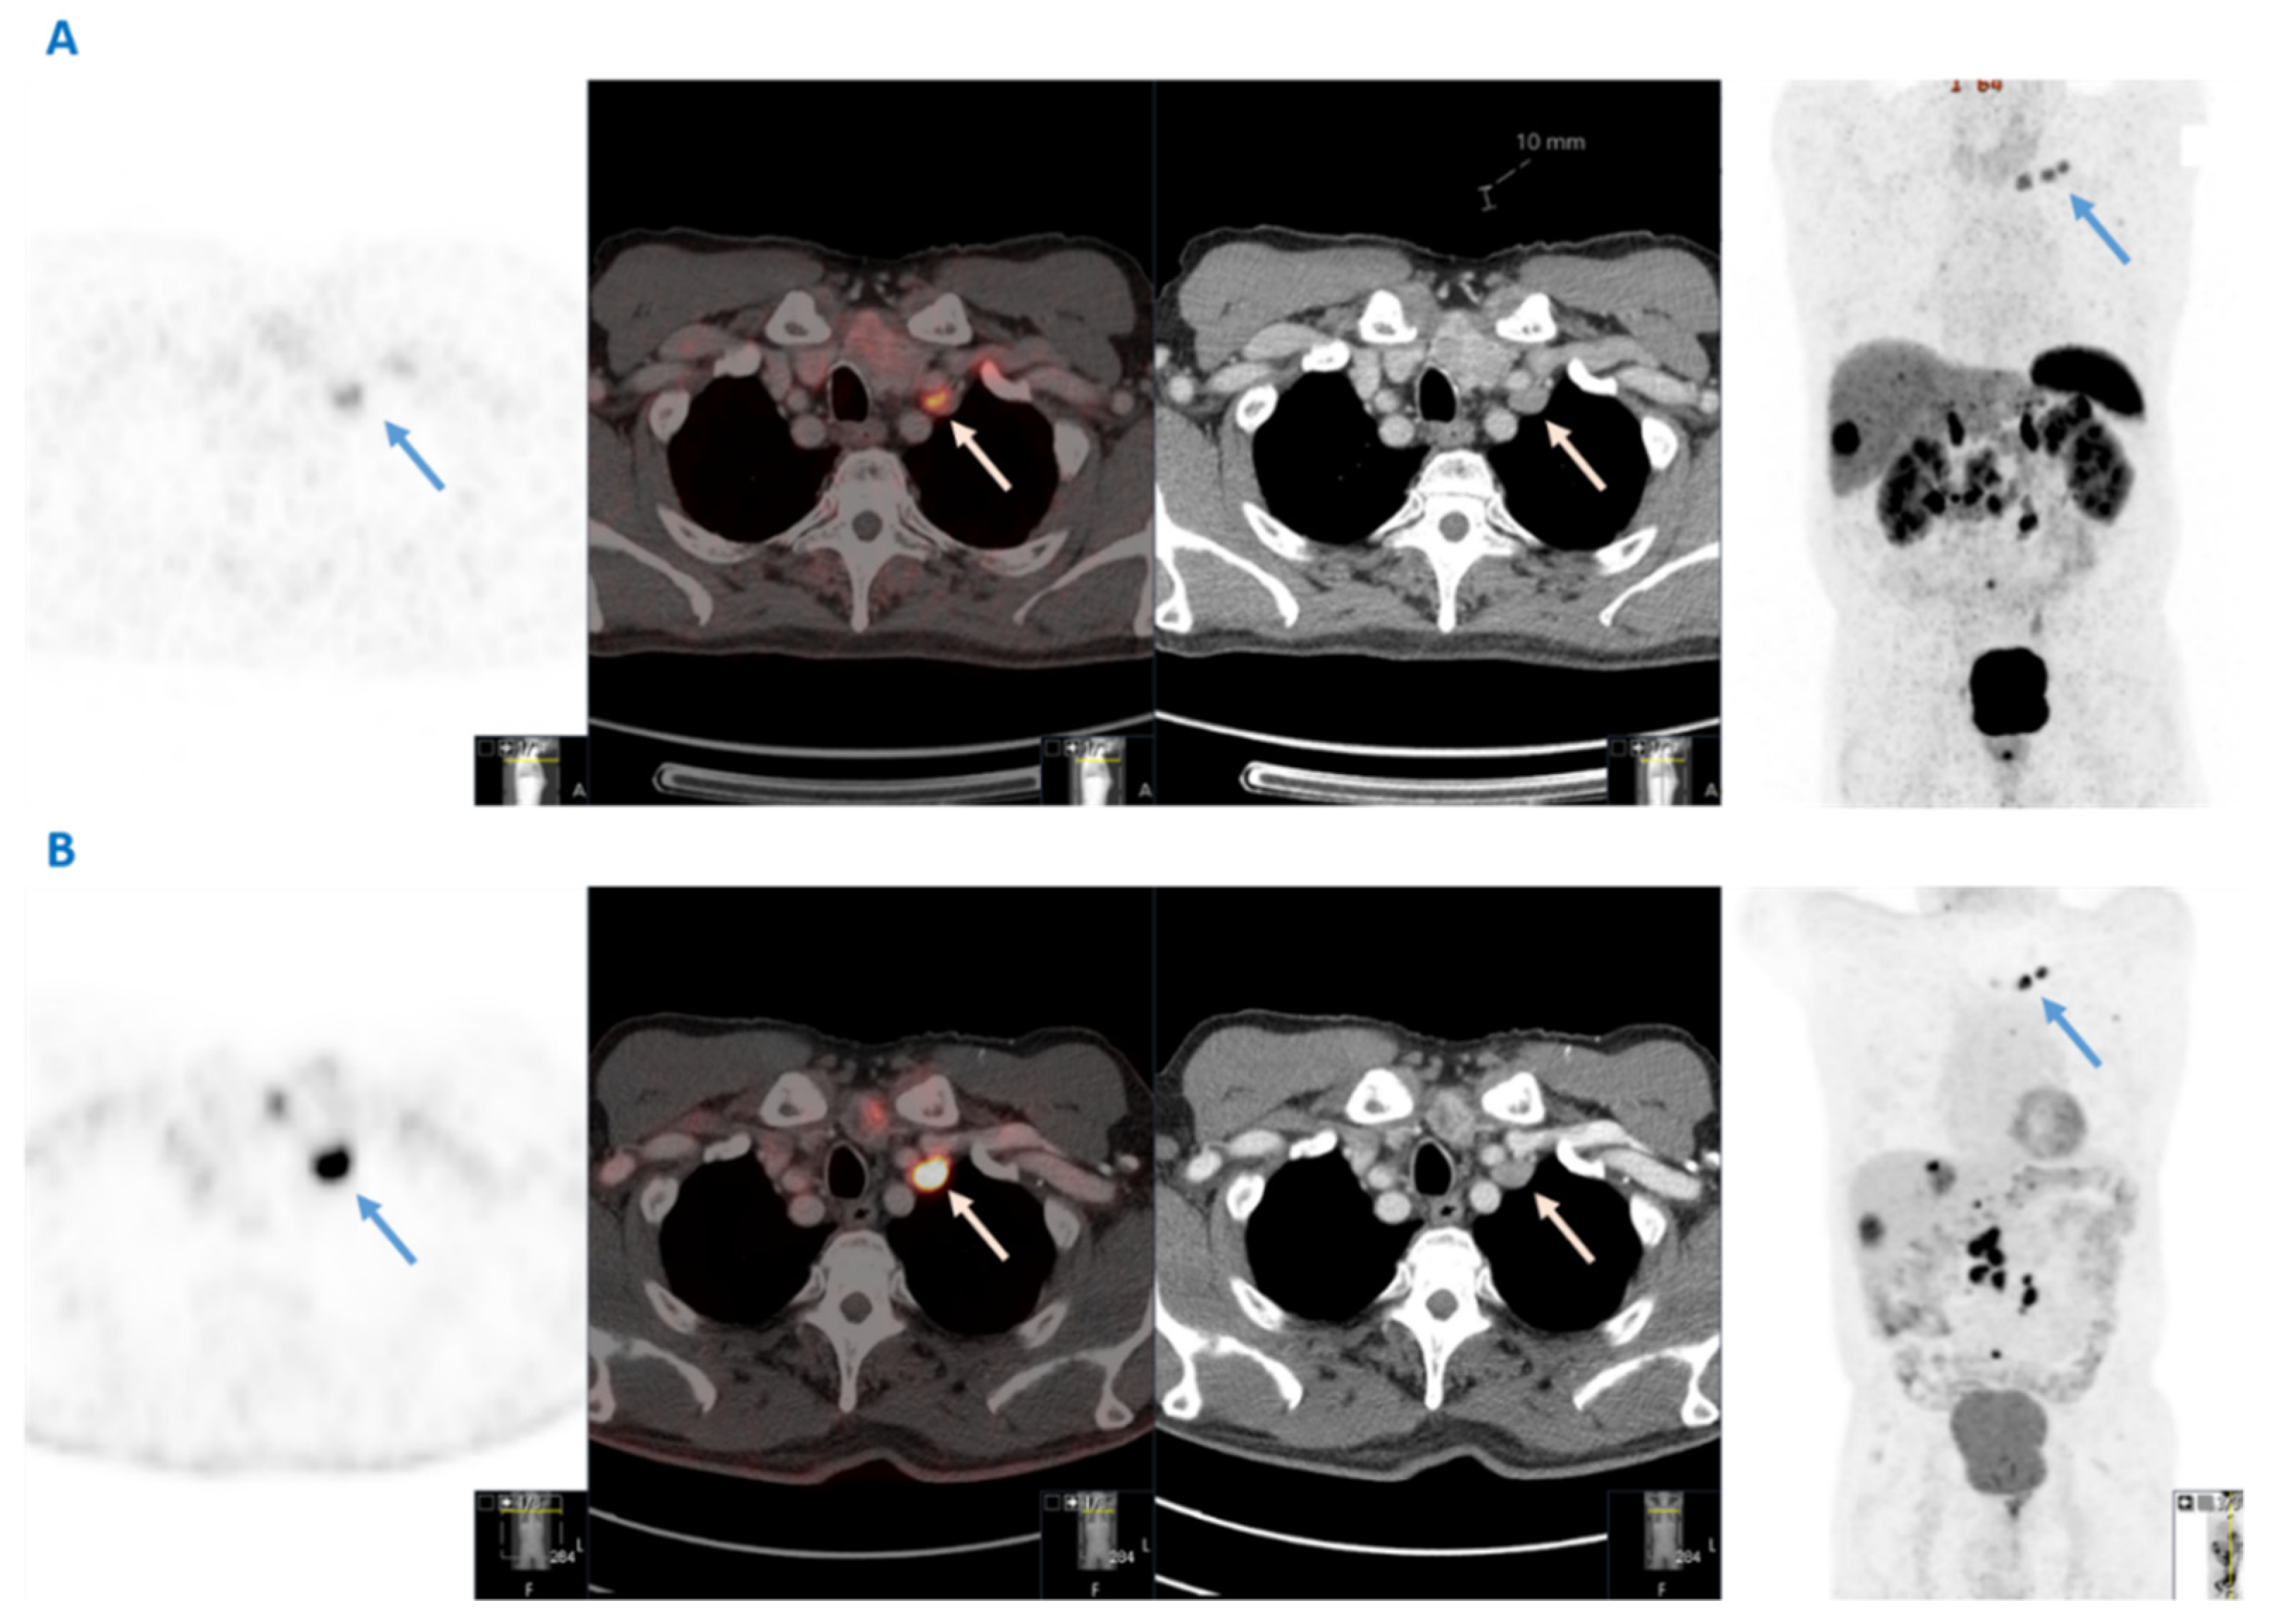

The initial detection of VM in the nine patients identified in this study was made by clinical examination in two patients, conventional CT in two patients and 68Ga-DOTATATE PET-CT in five patients. Overall, in two out of four patients with synchronous VM, the presence of VM itself led to the SI-NET diagnosis. Importantly, all VM lesions were somatostatin receptor positive in this series in subsequent functional imaging. Histopathological confirmation of VM secondary to SI-NET was obtained in five patients for diagnostic purposes through core needle biopsy (n = 3) or surgical resection (n = 2) of the left supraclavicular nodes. 18F-FDG PET-CT was performed in only three patients, in two of whom the VM lesion was FDG positive. The CT scan, 68Ga-DOTATATE PET-CT and 18F-FDG PET-CT imaging of a SI-NET patient with VM are shown in Figure 1.

In addition, G1 and G2 SI-NET patients may also have 18F-FDG-positive tumors initially or may develop 18F-FDG-positive lesions during follow-up, as demonstrated in Figure 1, with important implications for therapy optimization and disease surveillance. Dual functional imaging could probably be considered prior to treatment initiation to delineate tumor somatostatin receptor expression and glycolytic metabolic activity in the context of a personalized treatment strategy at least in G2 patients with Ki67 in the higher levels. Baseline dual-functional imaging assessment in higher grade SI-NETs with advanced tumor burden could be used for the selection of patients requiring PRRT or other systemic treatments as well as the prognostic evaluation of the disease [21]. Therefore, as G2 tumors were more often associated with the presence of VM, dual functional imaging could probably be considered in a subset of SINET patients of higher grade and more advanced disease at baseline, with the aims to accurately define metastatic extent and tumor aggressiveness.

Figure 1. Dual functional imaging of a patient with a G2 small intestinal neuroendocrine neoplasm and Virchow’s node metastases (blue and white arrows), both 68Ga-DOTATATE- and 18F-FDG avid. (A) From left to right: 68Ga-DOTATATE PET; fusion; computed tomography; and maximum intensity projection (MIP) images (B) From left to right: 18F-FDG PET; fusion; computed tomography; and maximum intensity projection (MIP) images.